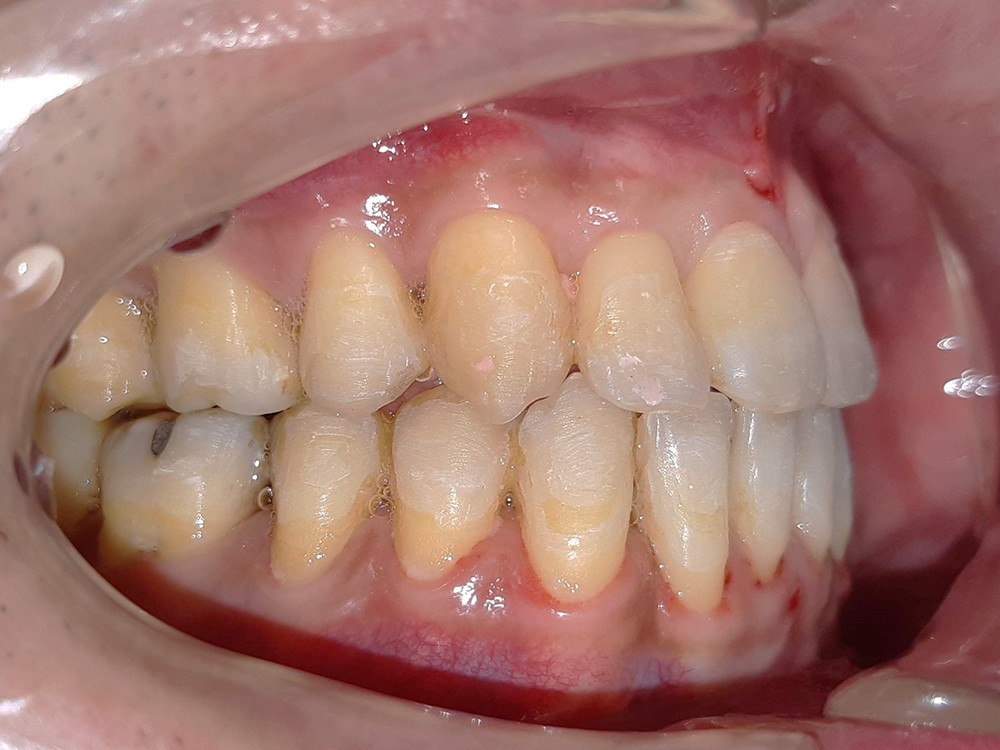

骨性戽斗案例(有手術) 矯正時間:大約1年。 戽斗未手術 戽斗手術後 戽斗未手術 戽斗手術矯正後 河馬牙醫診所 Dent.Hippo 台中市西屯區重慶路270號 04-23169788 營業時間:早上 9:00~12:00下午13:30~16:30晚上19:00~21:00週一到週六,每周日固定休診 線上預約 河馬牙醫患者好評